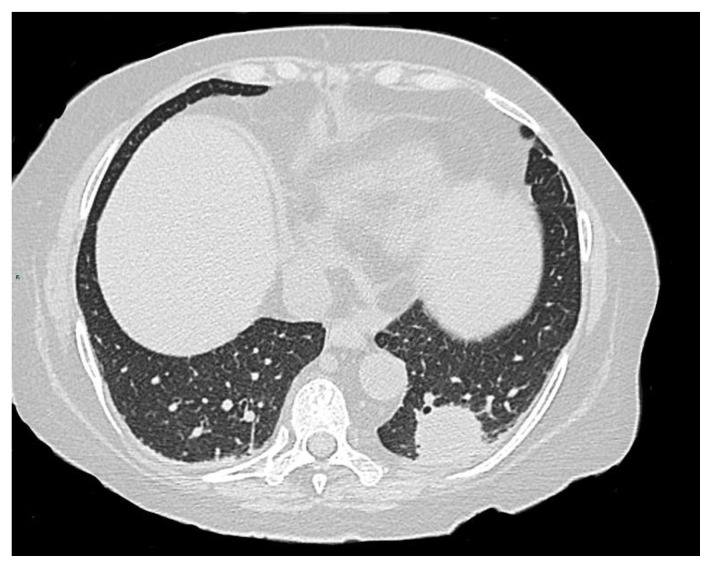

Results: We accrued 62 patients, of whom 7 (11,3%) tested positive, without any symptoms or signs of active TB, and 2 (3,2%) resulted as indeterminate. All positive patients started prophylaxis with isoniazid 300 mg daily, while patients whose test was indeterminate did not receive any prophylaxis. Active TB was excluded by imaging, as well as microscopic, cultural, and molecular examination on bronchoalveolar lavage if signs of any infection were detected. During the 46 months of observation, no patients developed TB reactivation.

Abstract Image